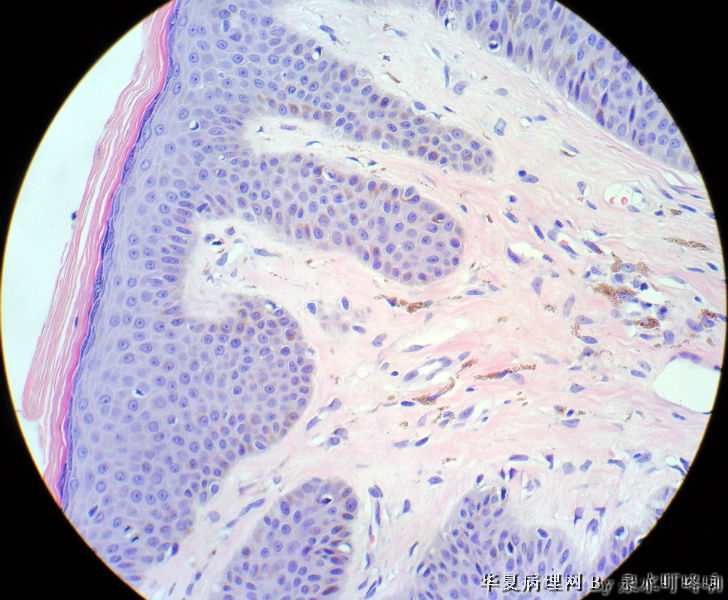

男,80岁,左耳后肿物十余年。

参考诊断

棘层肥厚型脂溢性角化症